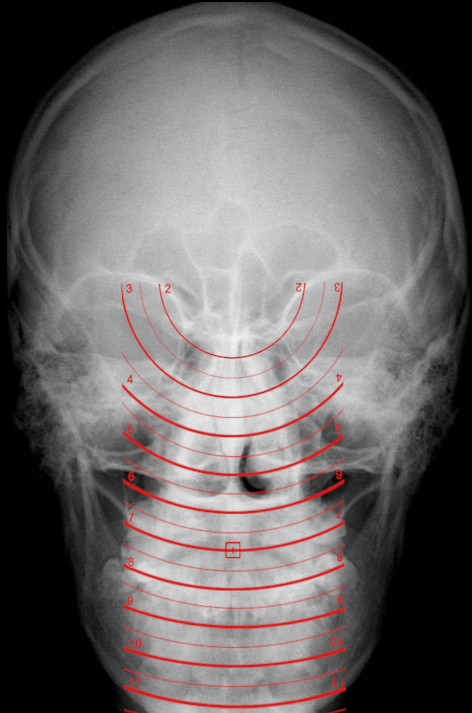

9.5.12. Condyle Circles Template

The condyle circles template is used to perform condyle circle measurements on occiptal condyles. Follow the instructions below to use this tool:

1.      Select the ‘Condyles circle’ from the advanced section of the chiropractic toolbox

2.      Click on the image and the template will appear on the image.

3.      To move the template: click on the template and drag it to the desired location.

4.      To resize the template: click on the any of the white points located on the outer corners and move it to adjust the dimensions.

5.      To rotate the template: click on the green point and a wheel will appear for you to click and rotate the template.

An example of this template is shown below: